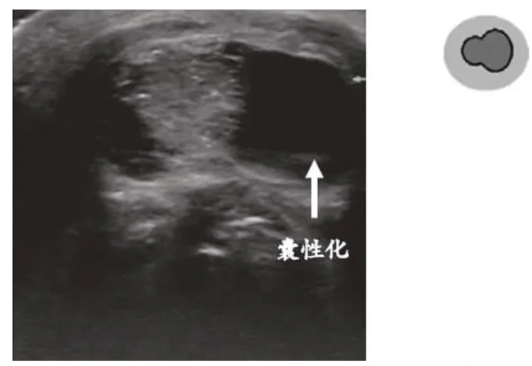

②囊性化(乳头状癌转移特征)

良性淋巴结多为实性,若有甲状腺乳头状癌病史,实性淋巴结内出现无回声区(囊性病变),转移几率>80%!